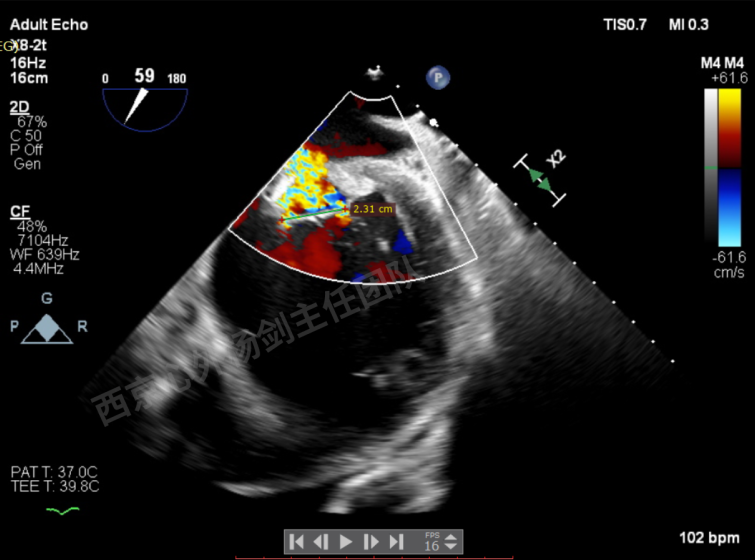

第二枚XT于第一枚夹子内侧瓣上调整

第二枚XT关闭后评估,trace

二尖瓣平均跨瓣压差1mmHg

释放后评估,反流降至1+,组织桥稳定